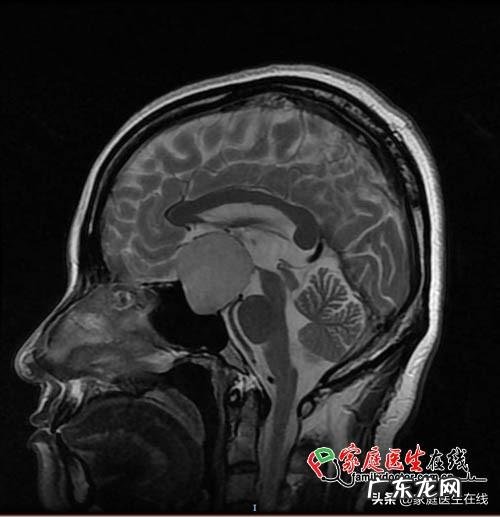

孕28周突发失明,一查就是个5公分“大瘤子”!33岁的黄女士(化名)结婚后一直在准备生孩子,无奈自然受孕不成功,最后通过试管婴儿如愿怀上了自己的宝宝 。今年6月份,孕28周的黄女士突然发现自己的左边眼睛看不见了,右眼视力也非常模糊,连放在眼前的手指多少根都难以辨别 。在她慌慌张张来到医院检查后,竟然发现自己脑部垂体的位置长了一个直径5公分左右的肿瘤 。

(入院MRI检查,垂体瘤已压迫视神经)

暨大一院神经外科副主任医师赖睿佳表示,垂体瘤的发病率在脑部肿瘤中排到第三位,仅次于胶质瘤和脑膜瘤 。垂体瘤大多是良性,但是随着肿瘤体积的变大,它可能会对视神经、视交叉造成压迫性影响,导致视力、视野的改变 。一般来讲,垂体瘤的发展过程比较缓慢,但是在患者怀孕期间,随着体内激素水平变化等原因,垂体瘤的增长速度会变大,就可能会出现视力急剧下降的情况 。而一旦患者发生失明,如果在1个月内能及时进行肿瘤切除手术,将有很大机会恢复视力 。